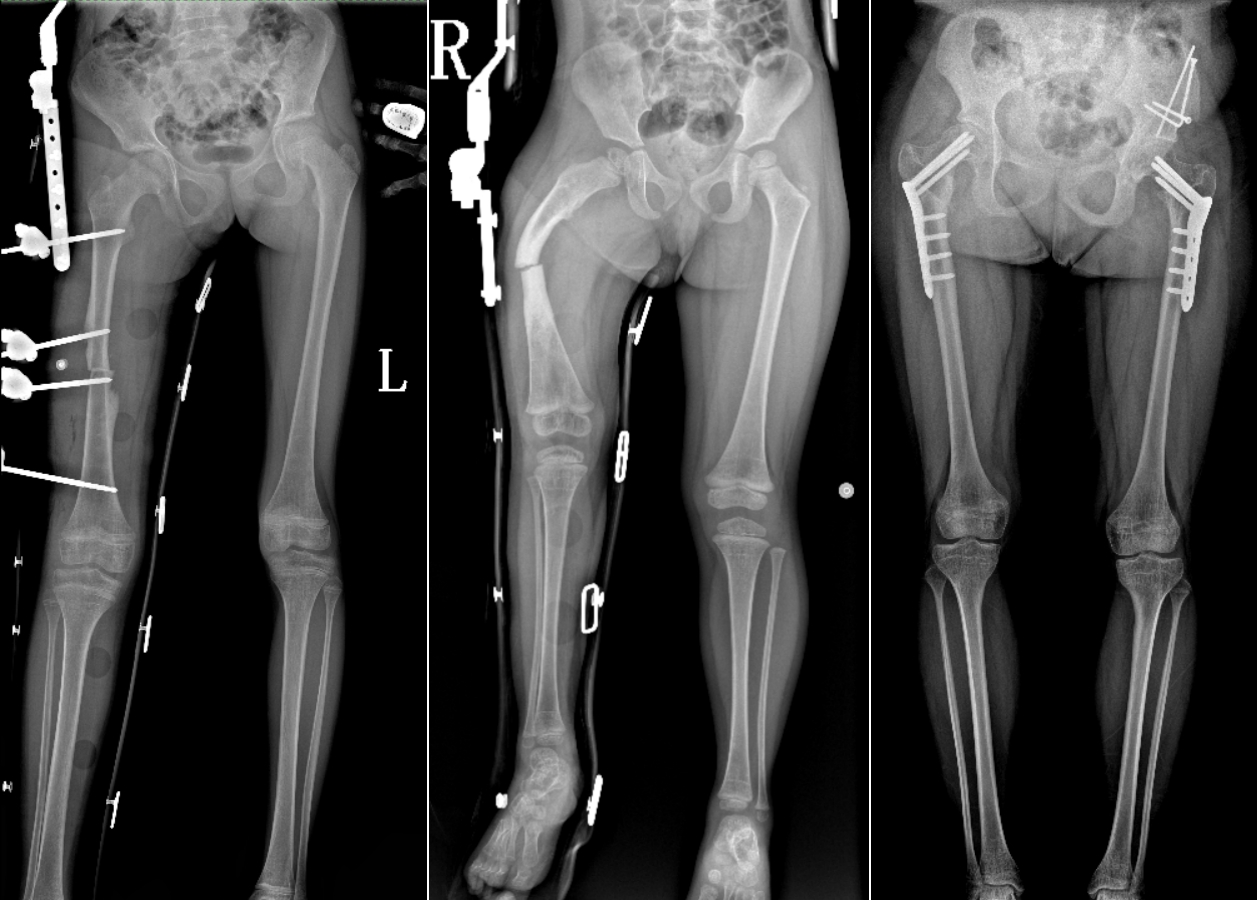

DR是臨床骨科的重要檢查手段之一。在骨科檢查中,脊柱矯形、長骨骨折、腰椎退行性病變等,需要采集脊柱、下肢全景圖像,輔助醫(yī)生臨床診斷,從而制定科學的治療方案,普愛醫(yī)療的大視野平板動態(tài)DR就像是一座橋梁,連接起現(xiàn)代醫(yī)療技術(shù)與當?shù)厝嗣竦尼t(yī)療需求。

普愛醫(yī)療自主研發(fā)的大視野平板動態(tài),采用17"*34"的有效視野,一次曝光即可得到全脊柱或全下肢影像。相較于多張攝影再軟件拼接的DR設備,PLX8600解決了拼接圖像存在密度不均勻,拼接處圖像配準和放大效應等問題,給臨床帶來了真正的大視野影像解決方案。

除了常規(guī)靜態(tài)攝影外,PLX8600的大平板具備動態(tài)透視和點片功能,能夠很好地觀察復雜部位病灶,有效地抓取關鍵幀,降低患者多次攝片的概率。如:全脊柱狀態(tài)評估、長骨關節(jié)活動度、下肢靜脈造影瓣膜功能評估、消化道功能評估、脊髓造影等更多大視野臨床應用,“多面手”都能輕松應對。